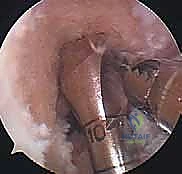

الخطوة الأولى: الفحص بالمنظار الجراحي 4K

يستخدم الدكتور